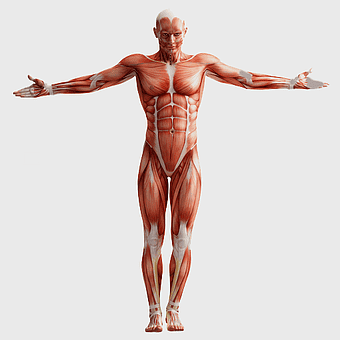

human anatomy diagram, muscular system illustration, human body muscles, fitness anatomy chart, skeletal muscle structure, human physiology study, muscle group analysis -

muscular system illustration, human anatomy diagram, fitness professional figure, skeletal muscle structure, muscular development, human body musculature, anatomical study -